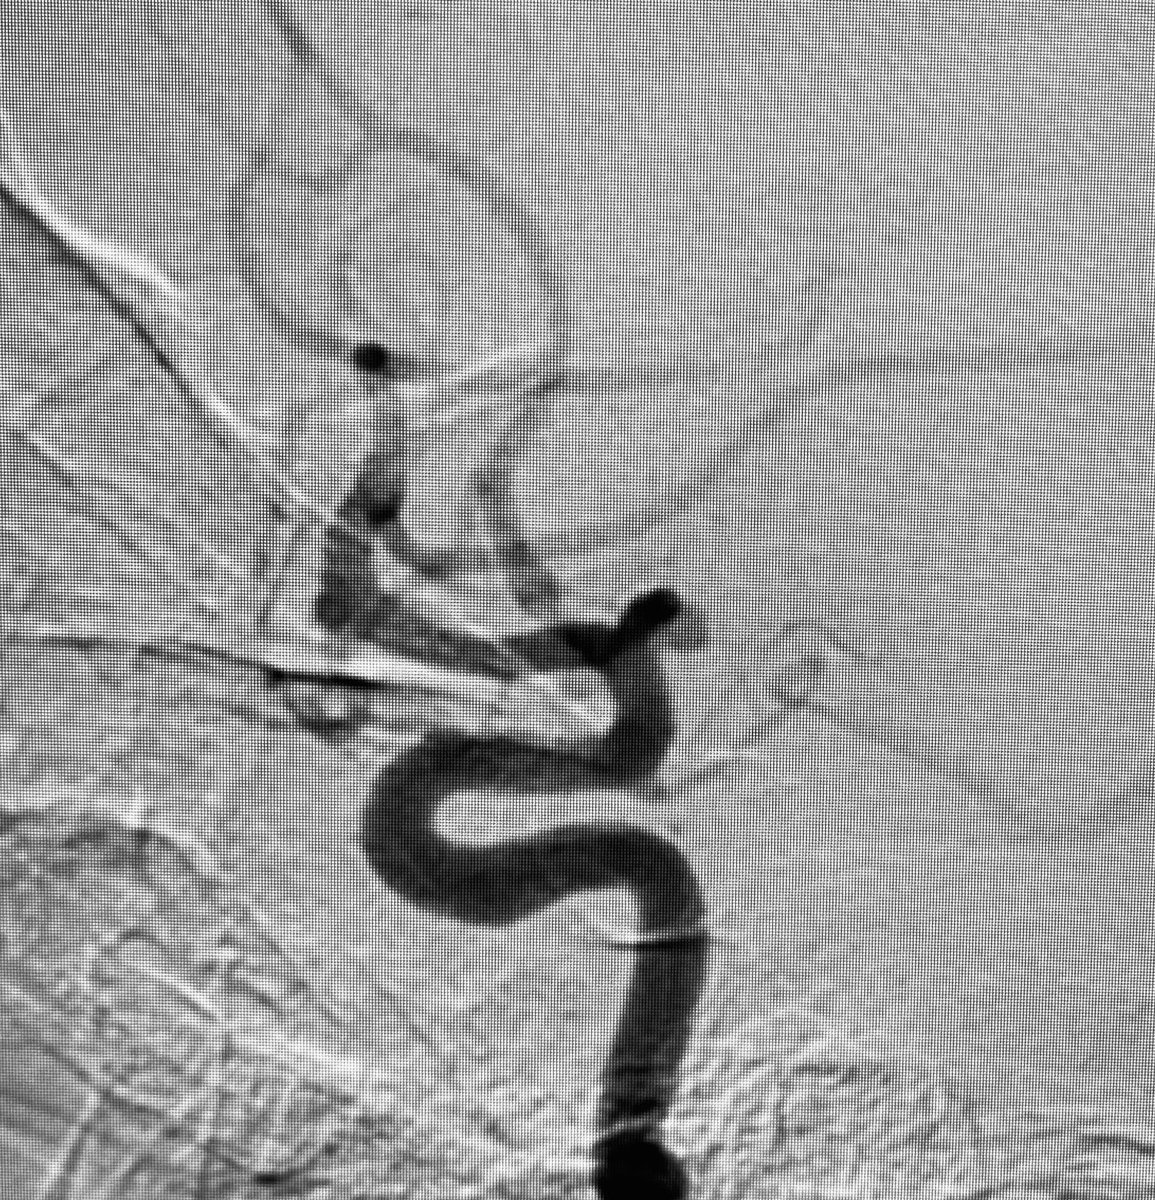

Case : AVM of leg with Pain & Limp.

Rx : AVM Embolization with Glue

#avm #embolization #irad #interventionalradiology #MedTwitter #Mumbai @ISVIRIndia @JVIRmedia @SIRspecialists @SIRRFS @cirsesociety @ApolloHosMumbai